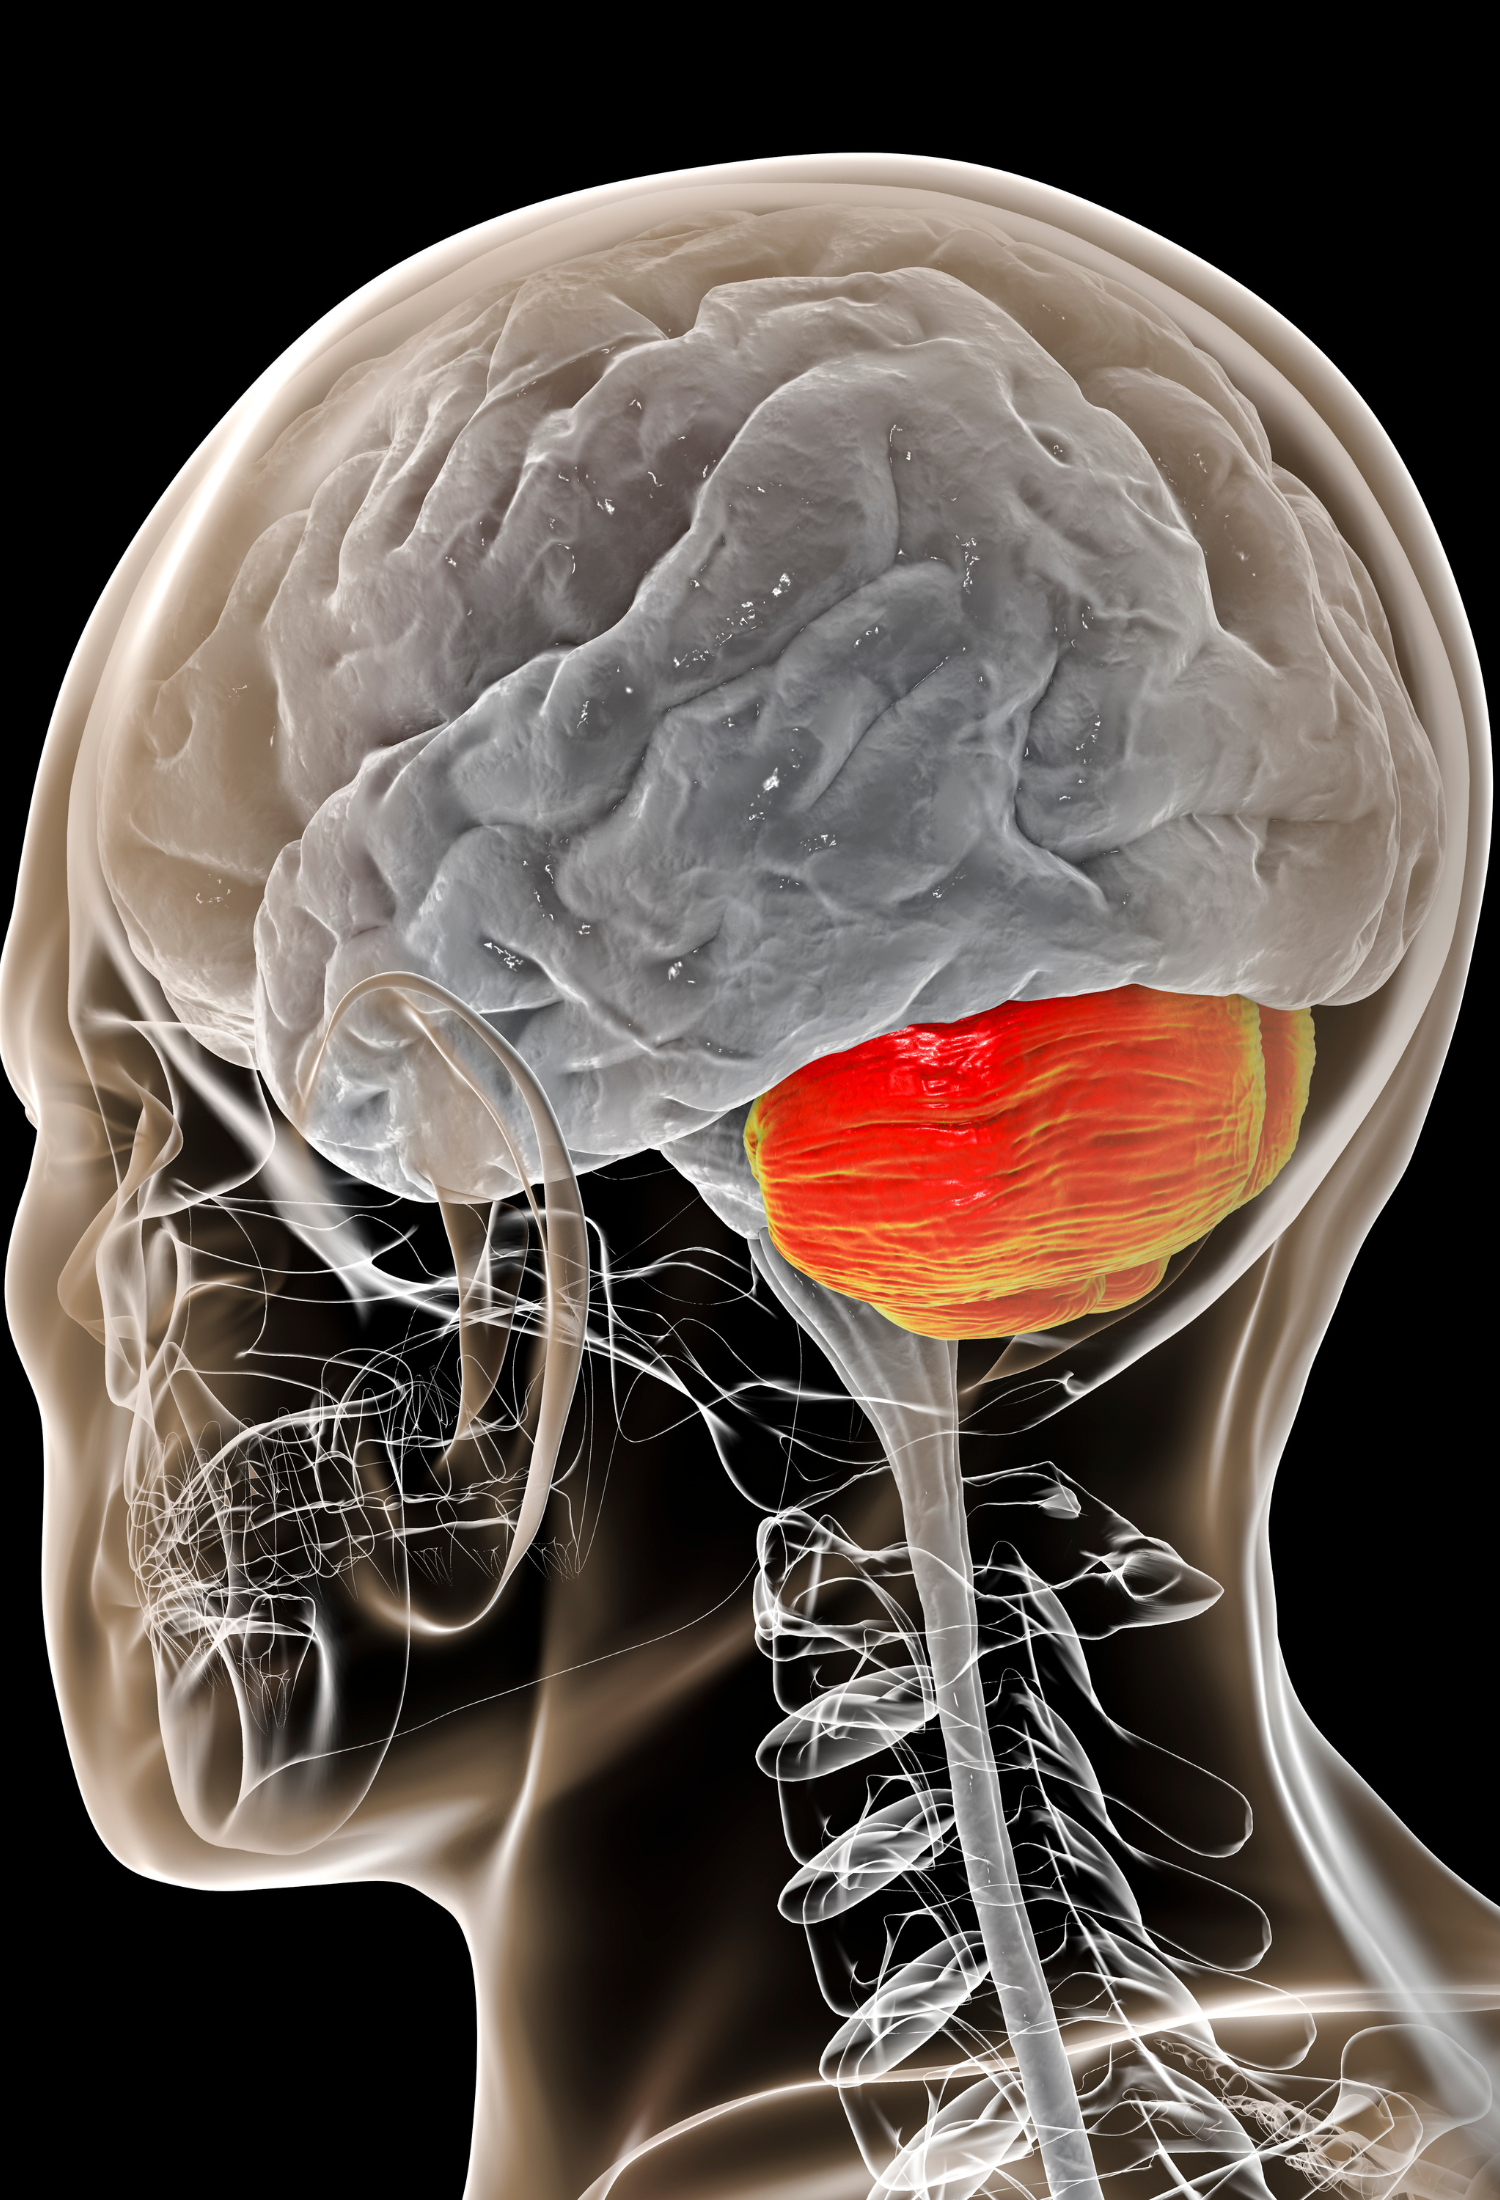

Alongside developing standards for fetal brain structures, researchers in the INTERGROWTH-21st project, which involved nearly 60,000 mothers and babies in eight urban areas in Brazil, China, India, Italy, Kenya, Omen, the UK and the USA, were also able to develop international standards for fetal cerebellar growth and Sylvian fissure maturation.

Cerebellar:

Relating to the part of the brain at the back of the skull that coordinates and regulates muscular activity

A paper co-authored by Professor Aris Papageorghiou, Professor Ana Namburete and colleagues from Leiden University also analysed fetal brain development to help understand whether changes in fetal circulation contributes to the delay in maturation of the cortex in fetuses with congenital heart defect (CHD).